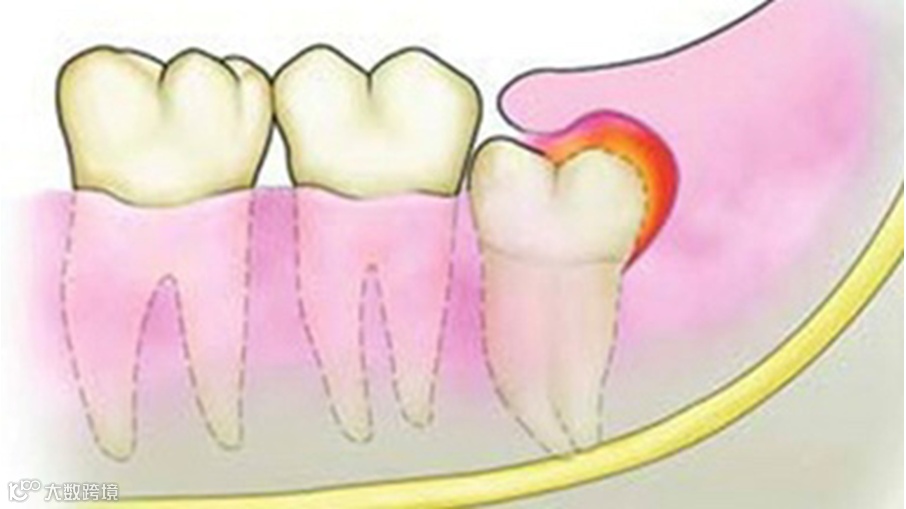

远古时代的人类用智齿咀嚼树根、树皮等粗纤维。由于人类食物日渐精细,颌骨退化变小,牙齿的大小及数量却未发生相应的变化,导致智齿没了“生存空间”,从而变成了“多余的器官”,擅长朝着各种方向野蛮“花式生长”。

智齿由于生长位置和用力方向不同,表现为部分萌出、萌出不正以及完全埋藏阻生。智齿阻生的发病率较高,引起智齿痛主要是以下几点原因导致的:

阻生的智齿牙冠周围软组织与牙齿之间形成一盲袋,引起食物、细菌的积存,抵抗力下降时,出现冠周炎是必然的。一般的消炎治疗治标不治本此冠周炎会反复发作。